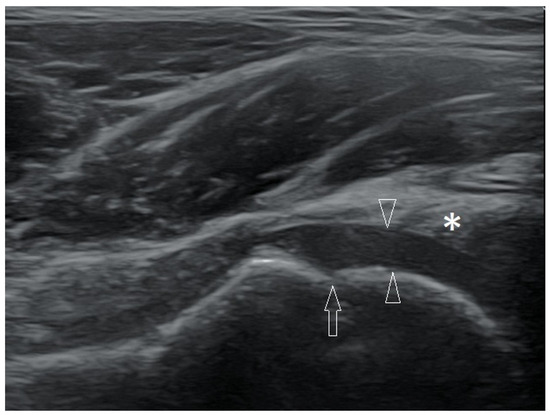

Basic Differences and Most Common Findings in Ultrasound Examinations of Musculoskeletal System in Children: A Narrative Literature Review

by Tomasz Poboży, Wojciech Konarski, Karolina Piotrowska-Lis, Julia Domańska, Kamil Poboży and Maciej Kielar

We present basic differences in the musculoskeletal ultrasound examinations between adults and children. Examiners who deal with adults on a daily basis have shared concerns about examining children. Such concerns may arise from the different approach to child ultrasounds, but they also come [...] Read more.

We present basic differences in the musculoskeletal ultrasound examinations between adults and children. Examiners who deal with adults on a daily basis have shared concerns about examining children. Such concerns may arise from the different approach to child ultrasounds, but they also come from differences in anatomical characteristics according to developmental age. We discuss the presence of growth plates, as well as non-mineralized parts of the bones. We also refer to the pathologies most often found in ultrasounds in early developmental stages. In the PubMed database, the set of keywords: “msk ultrasound in children”, “pediatric msk sonoanatomy”, “coxitis fugax”, “pediatric Baker’s cyst”, “Baker’s cyst ultrasonography”, “bone septic necrosis in ultrasonography”, “ultrasonography in juvenile idiopathic arthritis”, and “ultrasonography in juvenile spondyloarthropathies”, was used to identify a total of 1657 results, from which 54 was selected to be included in the article. We discuss the problem of osteochondritis dissecans, Osgood-Schlatter disease, examples of ligament injuries (especially in relation to the knee and ankle joints), exfoliation of growth cartilages, osteochondroma, exudates and inflammations affecting joints, and Baker’s cysts. In this way, we have collected useful information about the most common diseases of the musculoskeletal system in children. Full article